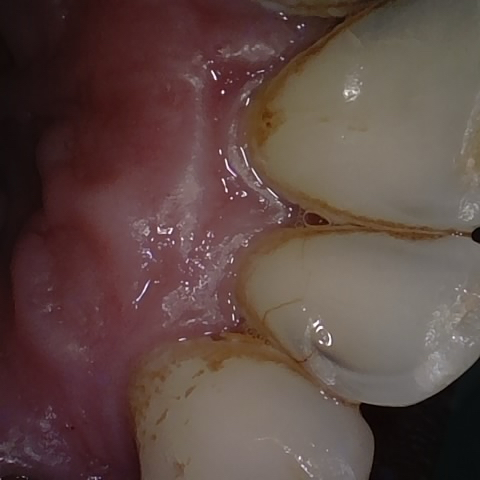

Annotated as "Good"